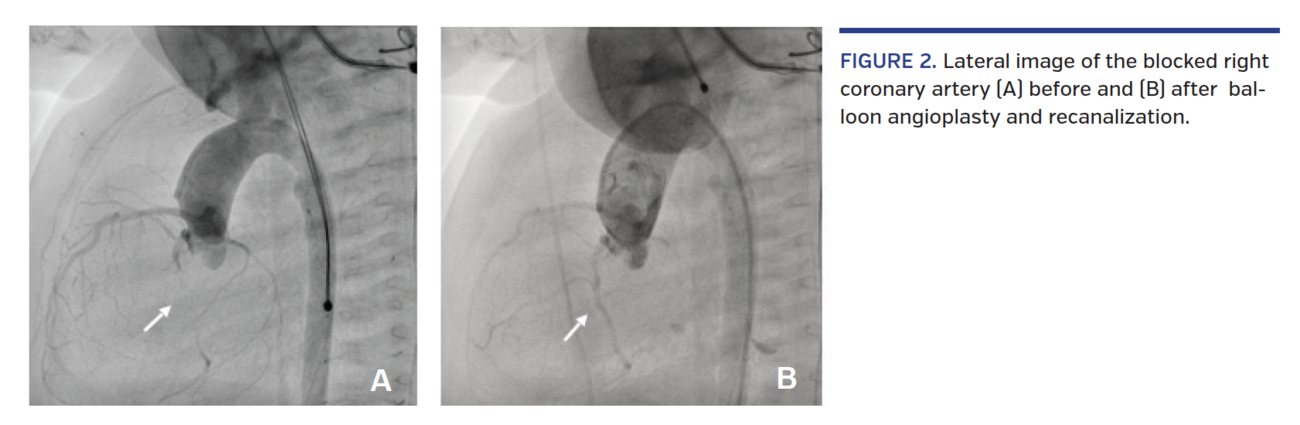

A 5-day-old term baby (weight, 3.5 kg) was transferred by air to our unit due to critical aortic stenosis (AS). Echocardiography showed severe left ventricular (LV) function impairment with diffuse LV hypokinesia and ejection fraction of 13%. The left atrium was moderately enlarged. The AS peak gradient was 70 mm Hg due to cusp fusion between the right and left coronary cusps. The newborn was taken to the cath lab, where right femoral artery access was easily obtained followed by heparin bolus of 50 IU/kg. Angiography of the ascending aorta showed a dysplastic, doom-shaped aortic valve with a negative flow jet toward the right anterolateral aortic wall and right coronary artery (RCA) occlusion at its mid segment, with its peripheral part reconstituted by collateral vessels from the left coronary artery connecting with the posterior descending artery (Figures 1A and 2A). Due to low systolic blood pressure (45 mm Hg) despite inotropic support with dopamine infusion, it was decided to proceed immediately with valvuloplasty and deal with the coronary occlusion afterward. During routine pre-valvuloplasty testing with pacing at 180 bpm, the patient developed ventricular fibrillation and was successfully cardioverted. Aortic valve annulus measured 7 mm; hence, balloon valvuloplasty followed, using a 7 x 2 Tyshak mini balloon catheter (B. Braun) with rapid pacing at 150 bpm. Disappearance of the balloon waist was noted and final hemodynamic peak gradient measured 15 mm Hg with no aortic regurgitation as seen on the repeat aortic angiogram. Interestingly, the angiogram also showed completely restored RCA perfusion, but acute pruning of the distal coronary network, implying embolization of the thrombus distally (Figure 1B).